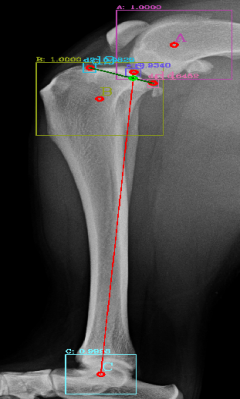

Following the identification of points of interests, and drawing of the lines of interest, i.e. the Functional Tibial Line (FTL) and the Medial Tibial Plateau Line (MTPL), another line is drawn such that the relation of new line and the FTL is 90°. Tibial plateau angle is the angle between this new line and the MTPL; this is shown in Fig. 3.

Most of the source dataset of over a thousand unique knee radiographs were distorted, had poor patient positioning, or were otherwise unfit for annotating. 250 of the original images were of sufficient quality to contribute to this effort. These images were set to have 6 different classes for training purposes, as mentioned and shown in Fig. 4. These were then trained using YOLOv3 [10] and the results of the predicted annotations are shown in Table I. From these predictions the centroids were extracted, which is then used to plot the FTL and MTPL. Then using the method mentioned in Section II, TPA is calculated. Examples of images, the region of interests detection and their respective TPA determination is shown in Fig. 6 and Table I:

| 6(a) | 20.537° | 22.67° | 24.8° | 22.9° |

| 6(b) | 17.354° | 17.62° | 18.7° | 16.22° |

| 6(c) | 19.473° | 19.53° | 20.03° | 18.24° |

| 6(d) | 23.369° | 27.37° | 29.03° | 25.8° |

| 6(e) | 18.435° | 15.5° | 17.65° | 16.8° |

| 6(f) | 19.699° | 18.24° | 20.22° | 18.59° |